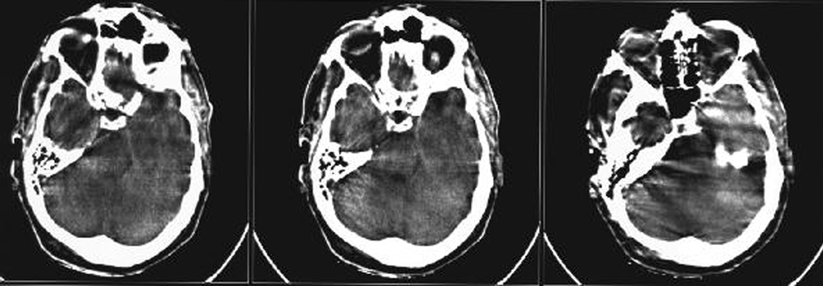

Untersucht wurden 313 Patienten (Durchschnittsalter 62 Jahre) mit akutem ischämischem Insult. Alle Patienten wiesen nur leichte Symptome auf, beispielsweise eine Gesichtslähmung, Sensibilitäts- oder Sprachstörungen. Die eine Hälfte der Studienteilnehmer erhielt innerhalb von drei Stunden nach dem Ereignis Alteplase i.v. mit einem oralen Placebo, die andere Gruppe bekam Acetylsalicylsäure p.o. und Placebo i.v.

Bezüglich des primären Studienendpunkts unterschieden sich die beiden Gruppen kaum: Drei Monate nach dem Insult wiesen rund 78 % der Lysegruppe und gut 82 % der mit ASS behandelten Patienten ein günstiges funktionelles Outcome auf.

Ob leichtgradig neurologisch beeinträchtigte Schlaganfallpatienten akut mit dem Fibrinolytikum oder mit ASS behandelt werden, scheint keinen Einfluss auf den Schweregrad späterer Behinderungen zu haben, schlussfolgern die Autoren um Dr. Pooja Khatri von der University of Cincinnati in Ohio.